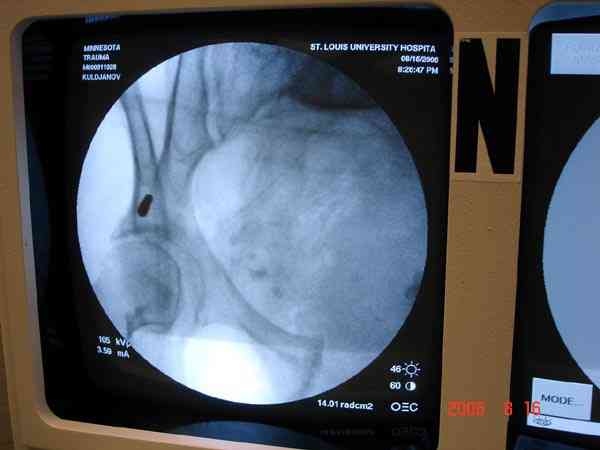

Прооперировали молодую девушку 32 лет спустя 9 мес после травмы. Имелся стойкий болевой синдром, неопороспособность левой н/конечности, моторные и сенсорные нарушения в левой голени и стопе, патологическая подвижность левой половины таза. Первым этапом закрыто в аппарате исправили деформацию ( в течении 2,5 нед). Вторым закрытое введение илиосакральных винтов в крестец (канюллированные 7,2 мм Chm) + туннелизация зоны псевдоартроза спицама Киршнера, реконструкция передних отделов таза, накостный остеосинтез . Аппарат частично демонтирпован, оставлена "передняя рама" После устранения деформации отмечен регресс неврологической симптоматики, уменьшение болевого синдрома. Интересующие вопросы: 1. Прогноз для сращения псевдоартроза крестца. 2. сроки нагрузки весом левой половины таза. Буду очень признателен за ваши мнения по этому поводу.A female 32 y.o. admitted to our unit 9 months after initial injury with pain, inability to bear weight at the left lower limb, sensor and motor disturbances in the left foot and tibia, with mobility of the left hemipelvis.At first closed reduction was performed by an external fixator within 2,5 weeks. After correction her pain decreased and some neurological progress was achieved. Now two iliosacral screws 7,2 mm were inserted, and anterior lesion was fixed by a plate. External fixator was partially unmounted, only anterior frame left in place.Images attached.How would you evaluate chances of healing of the sacrum with the current position?When would you allow weight-bearing of the left leg?THX in advance.

Мне нравится ваша закрытая репозиция девятимесячного ложного сустава, не знаю насчет туннелизации, но шурупы в 7.2 это серёзная конструкция. При стабильной фиксации крестец должен срастись, только я бы держал передний фиксатор до шести недель, костыли, а полную нагрузку разрешить через 12 недель.